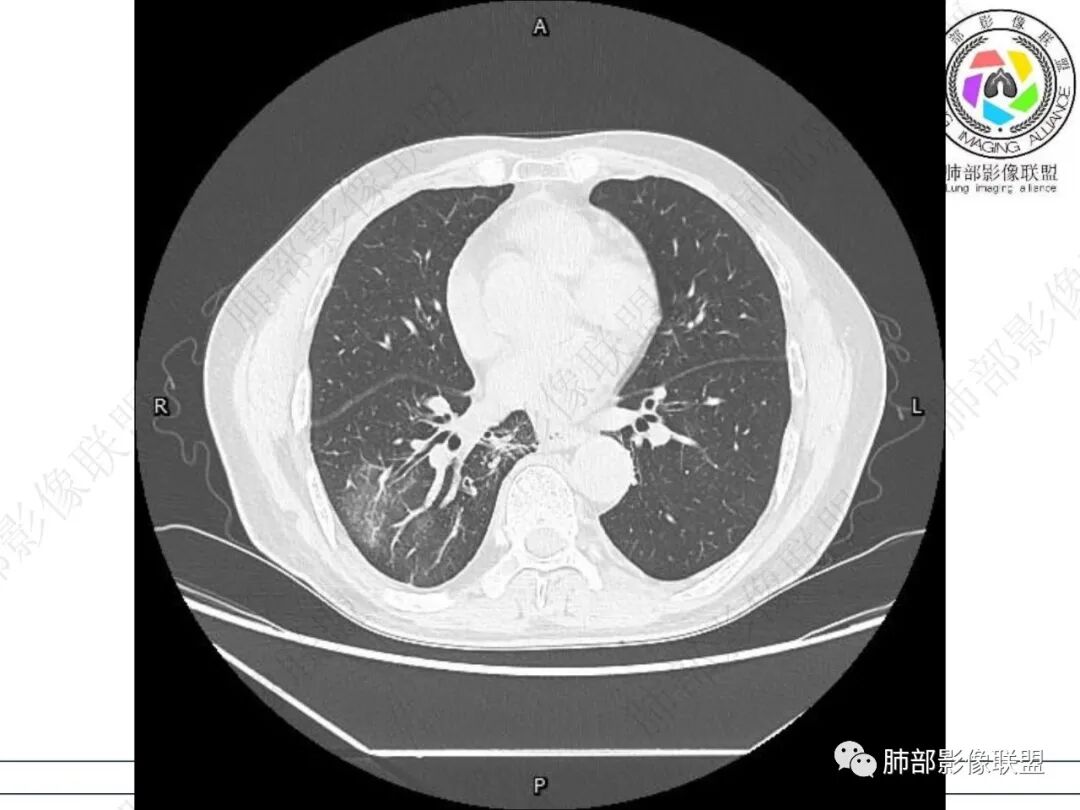

右肺下叶背段可见斑片状、条片状高密度影,支气管扩张,周围伴有磨玻璃影,边界欠清,纵隔窗:可见脊柱偏右侧可见斑片状影,与食管交界面欠清,食管形态不规则,考虑食管支气管瘘?食管异物穿孔?支气管异物?建议食管镜及支气管镜检查。

男性69岁,咳嗽,咳痰10多年。两肺下叶有支气管扩张的改变,右肺下叶背段的片状实变阴影,有支气管的扭曲样穿行,有病灶的收缩,以及沿着支气管的 播散病灶,肺门纵隔内支气管隆突的上下呈大片状的实变影,结构比较混乱,食管显示的不清楚,伴有多发的淋巴结增大。临床上主要提及呼吸道的症状,但是没有提及消化道的症状。另外还见到肝内有多发的低密度病灶,考虑囊肿。

右肺下叶沿肺叶肺段分布斑片、条片状影,以下叶背段为显,边缘模糊,内可见支气管走行,局部支气管管壁增厚,右侧胸腔少量积液。纵隔隆突下可见不均匀软组织密度影,与周围结构分界不清,内见气体密度影,与食管及相邻右肺支气管之间未显示通道。邻近食管下段壁明显不规则增厚,增强后食管管壁明显不均匀强化,可见线样强化的连续完整粘膜影。

右肺下叶片影,气道相关,符合感染性病变。纵隔隆突下软组织密度影,异常气体影,长病程,起病缓慢,提示存在气管或食管瘘。食管镜未见明显新生物形成,临床未提供进食或饮水呛咳临床表现,综合分析应该考虑支气管瘘的形成。